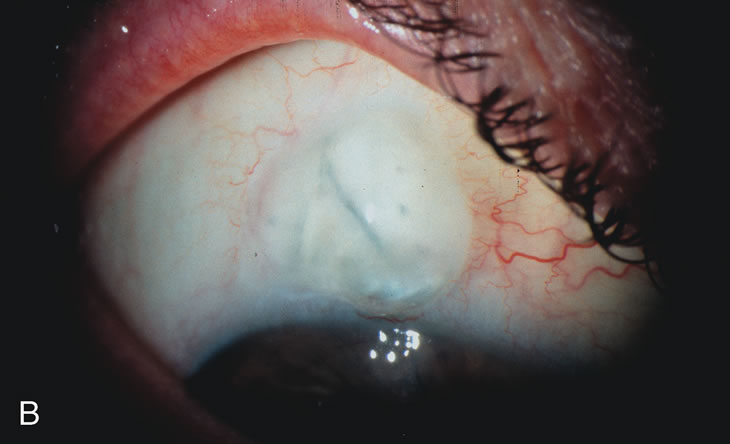

Fig. 5. Anterior chamber angle changes associated with lens extraction and PCIOL This 65-year-old Vietnamese woman has a long-standing history of chronic angle-closure glaucoma treated with laser peripheral iridectomy. The optic nerve demonstrated mild glaucomatous damage and IOP was moderately controlled on two antiglaucoma medications. The cataract was removed through temporal clear corneal phacoemulsification with foldable acrylic IOL. A. Symptomatic cataract in narrow-angle glaucoma eye with patent iridectomy. B. Intraoperative goniophotograph showing crowding of angle with increasing narrowness due to phacomorphic component. C. Intraoperative photograph showing temporal clear corneal approach with IOL in the capsular bag. D. Intraoperative goniophotograph demonstrating deepening of chamber angle following lens extraction. Proposed theories for IOP reduction following lens extraction with complete wound closure: